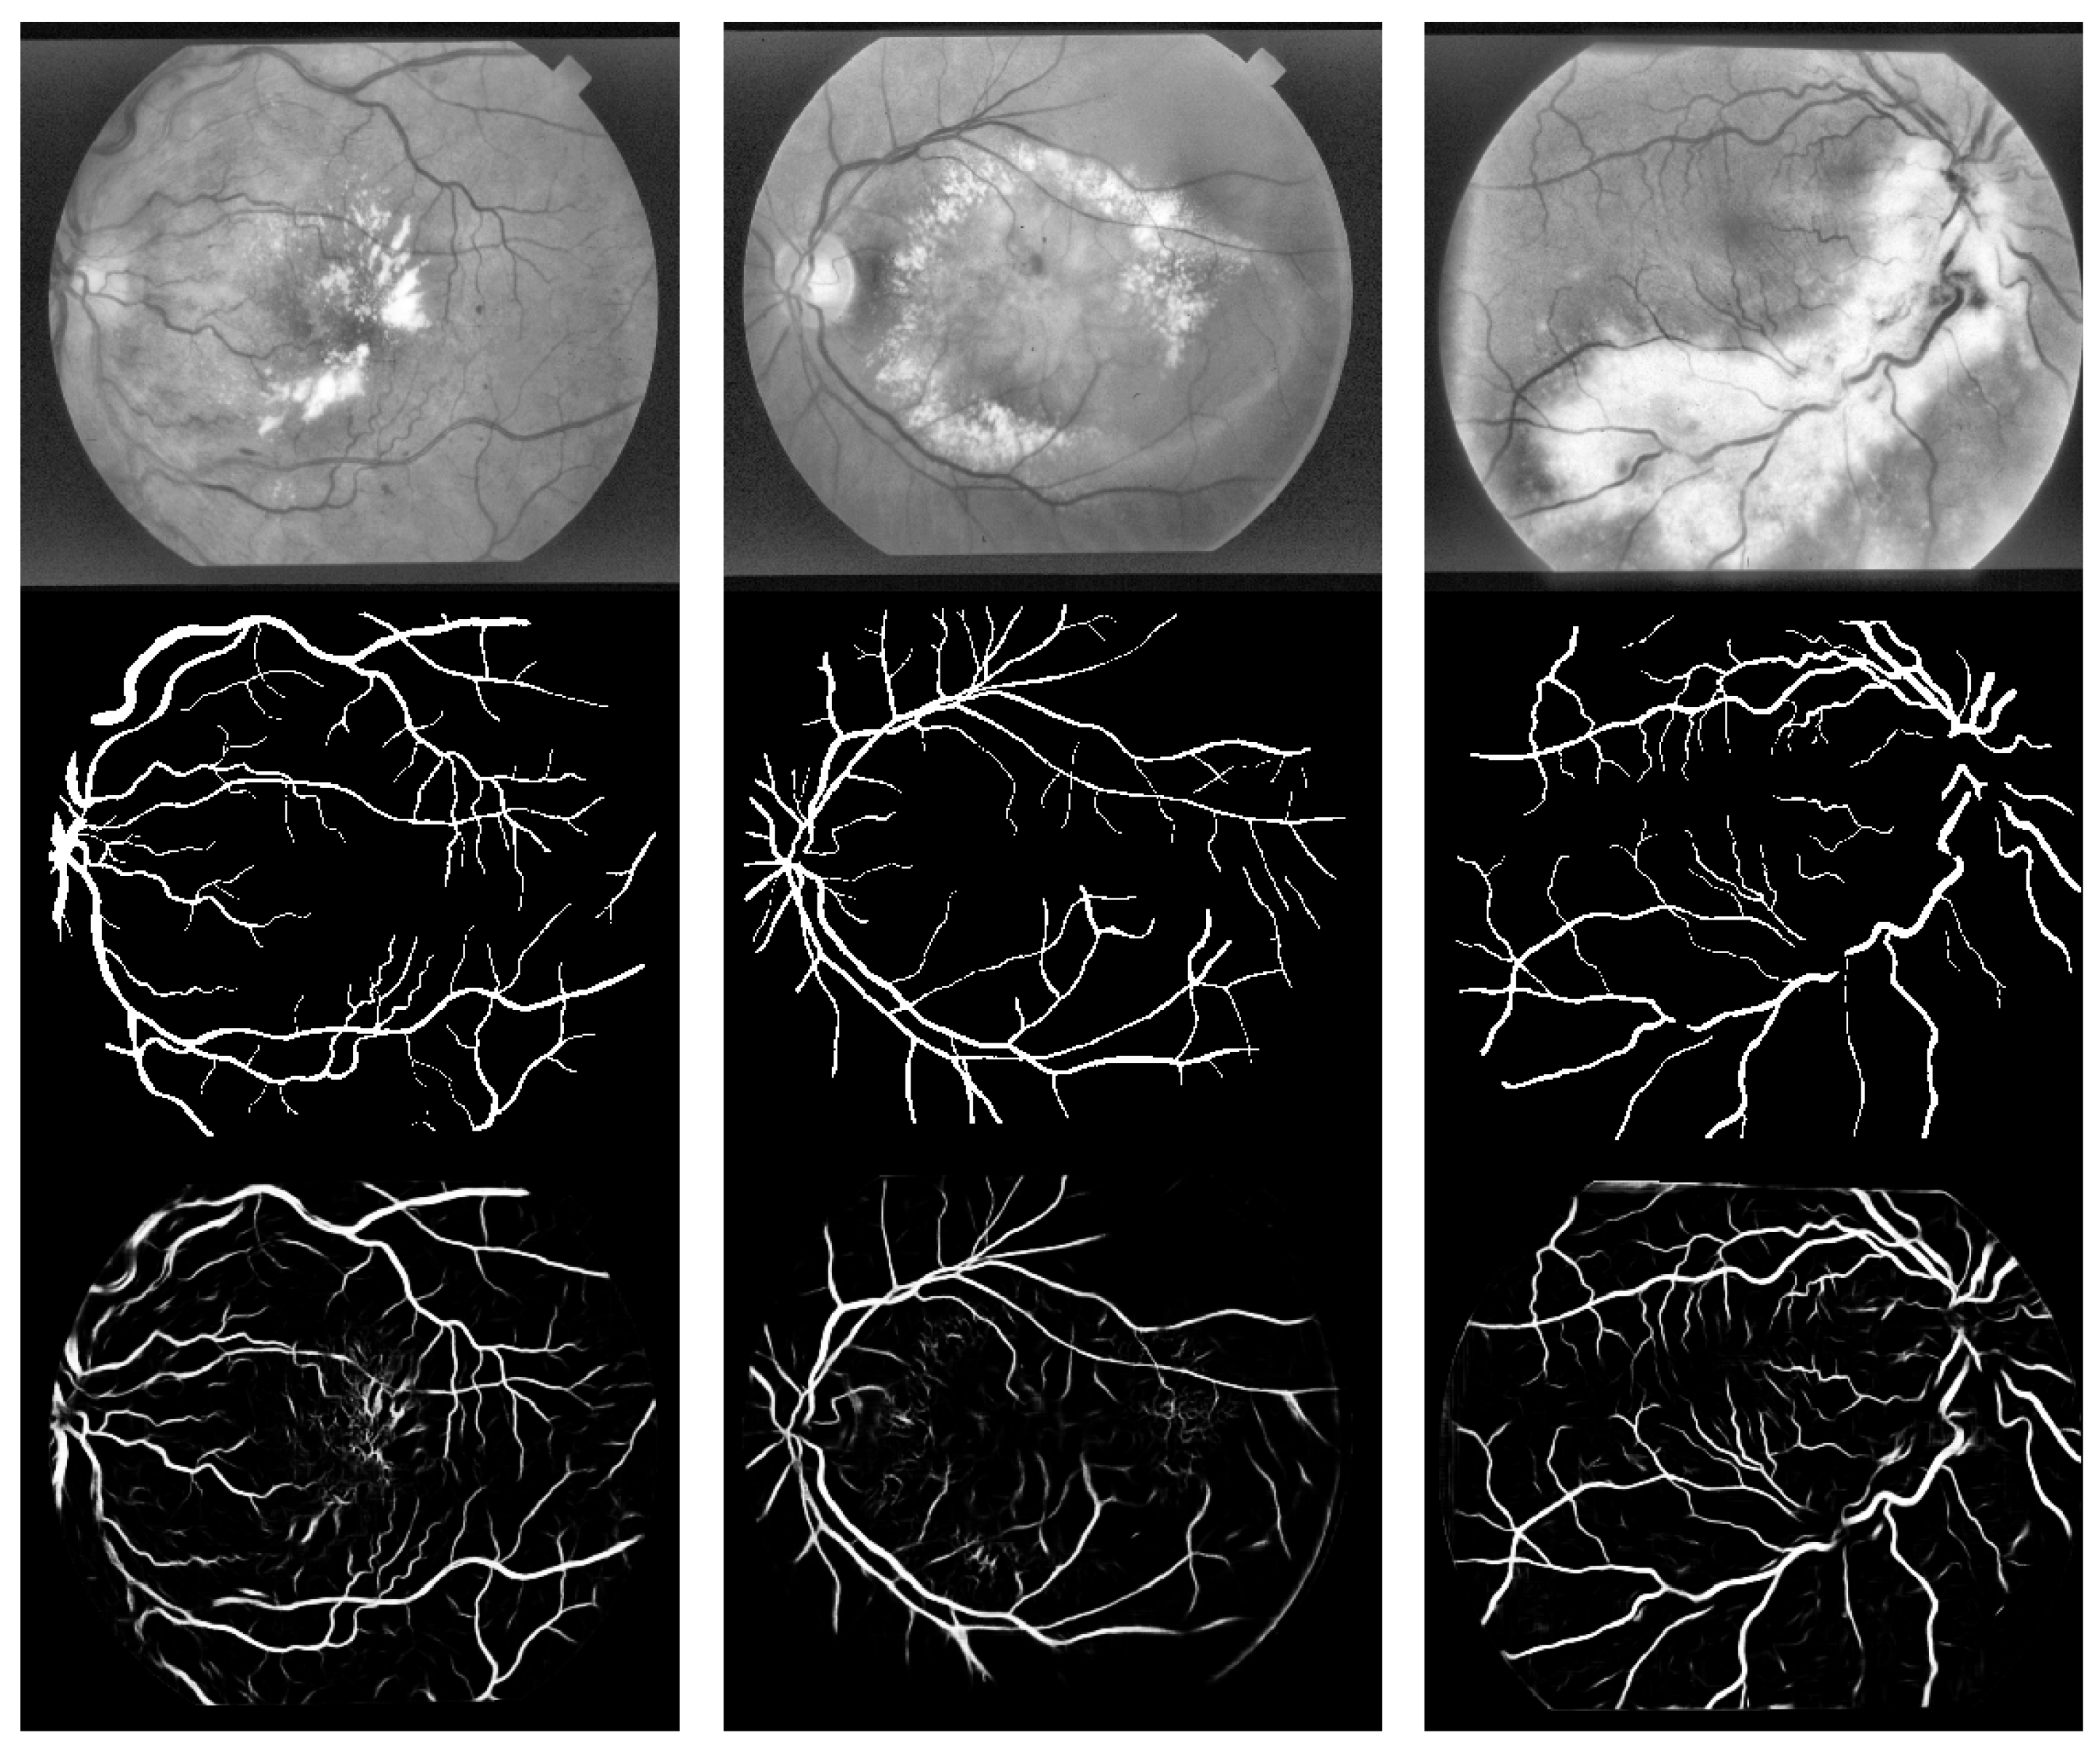

For some of the more severely affected retinal images in the STARE dataset, we have also included segmentation results in Figure 12. In these figures, the first row shows three grayscale retinal input images, the second row presents the corresponding ground truths, and the third row displays the segmentation results achieved by our proposed method. It can be observed that for those severely affected retinal images, where the vessel pixels are distorted due to interference from lesion areas, our method can still segment the vessels. However, the overall segmentation performance on these diseased images is not as good as on healthy images.

Figure 12. Segmentation results of severe lesion images based on the STARE dataset.

Symmetry 17 01462 g012